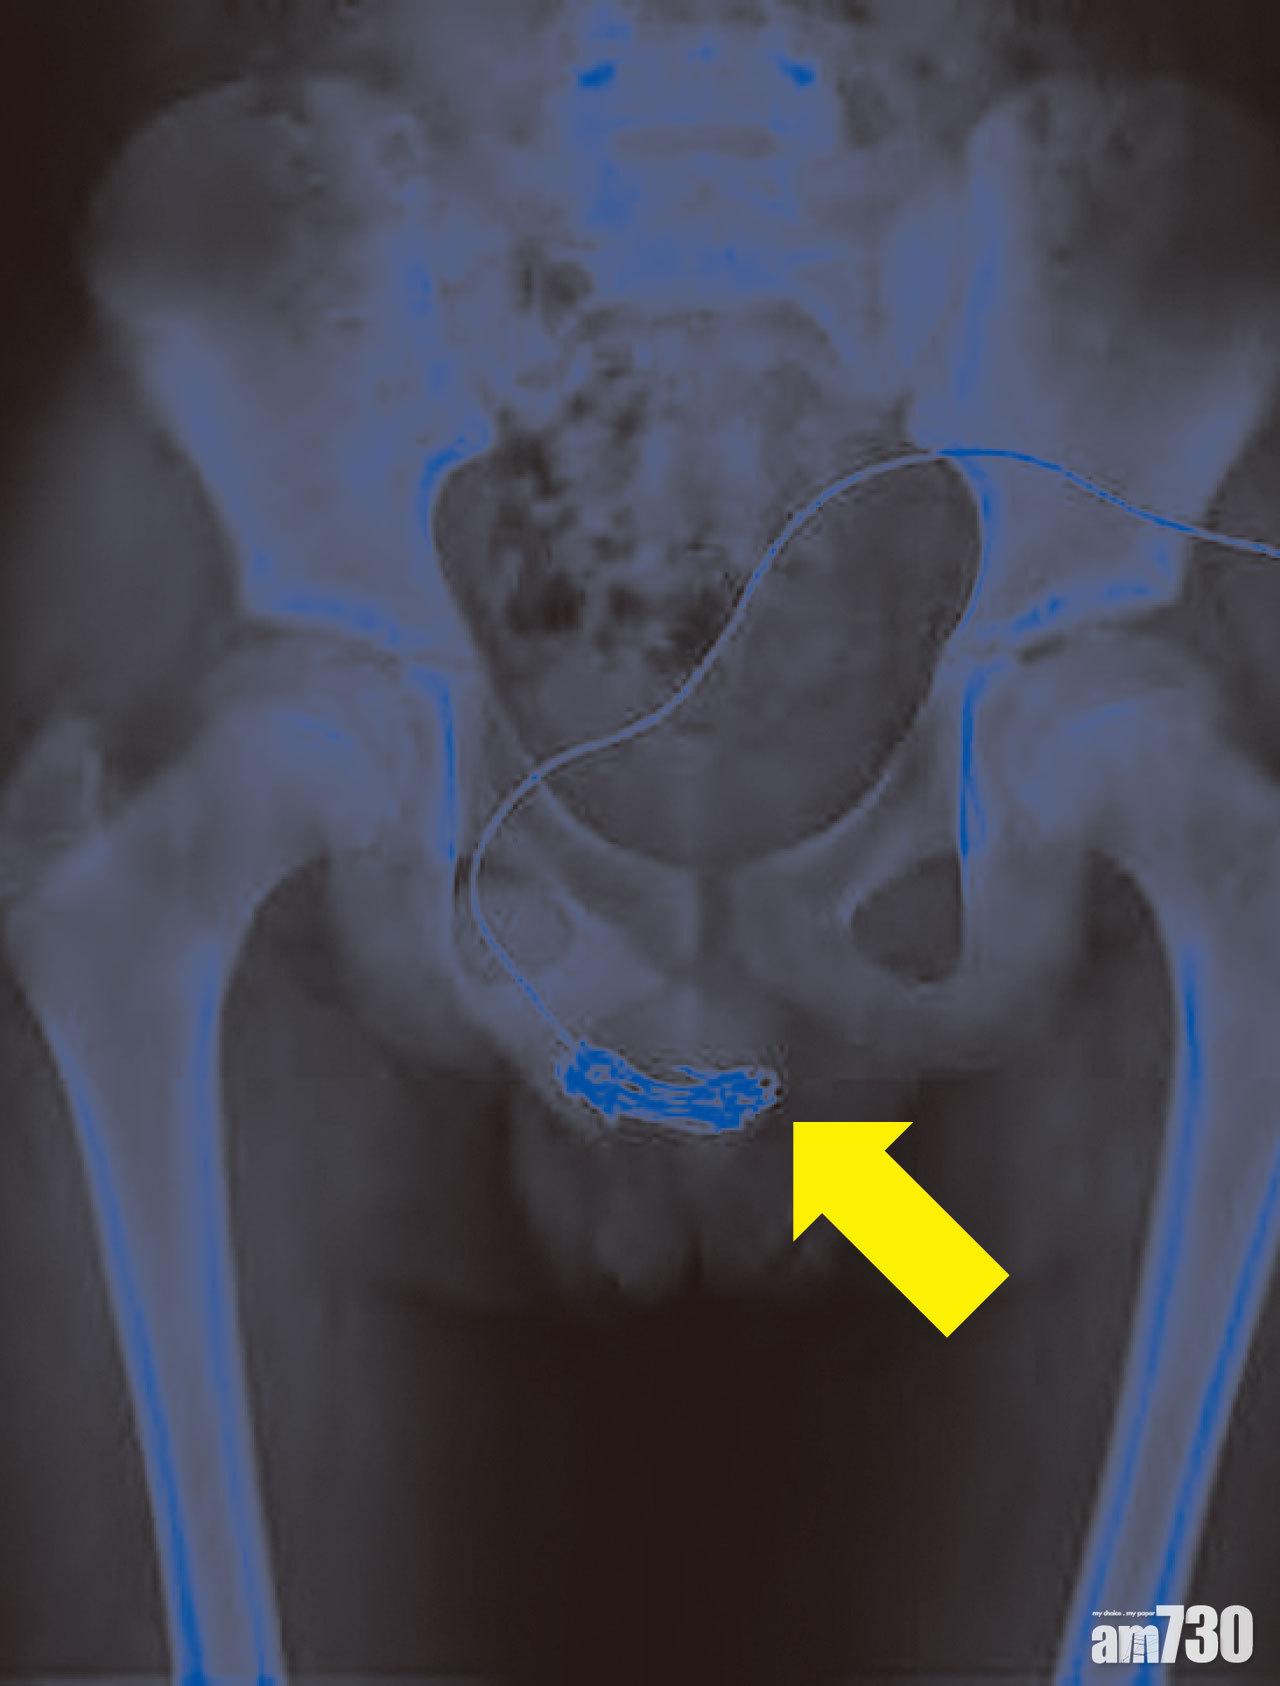

(圖1、香港醫學雜誌圖片)

去年6月,一名12歲男童把20厘米的電線塞入尿道,希望止癢,卻導致疼痛和有血尿,他和母親嘗試抽出不果後求醫。威爾斯親王醫院團隊為他進行X光檢查後,先後以凝膠和全身麻醉嘗試把電線牽引出來無果,最終要切開尿道中段移走電線(圖1)。男童留院兩日後出院,但仍要「孭尿袋」兩周。男童母親表示,一家早前從台灣移民來港,兒子難以適應、融入日常和學校生活,加上長期毋須回校獨留家中,影響情緒健康。男童之後亦被診斷有自閉傾向、對電線有強烈興趣。